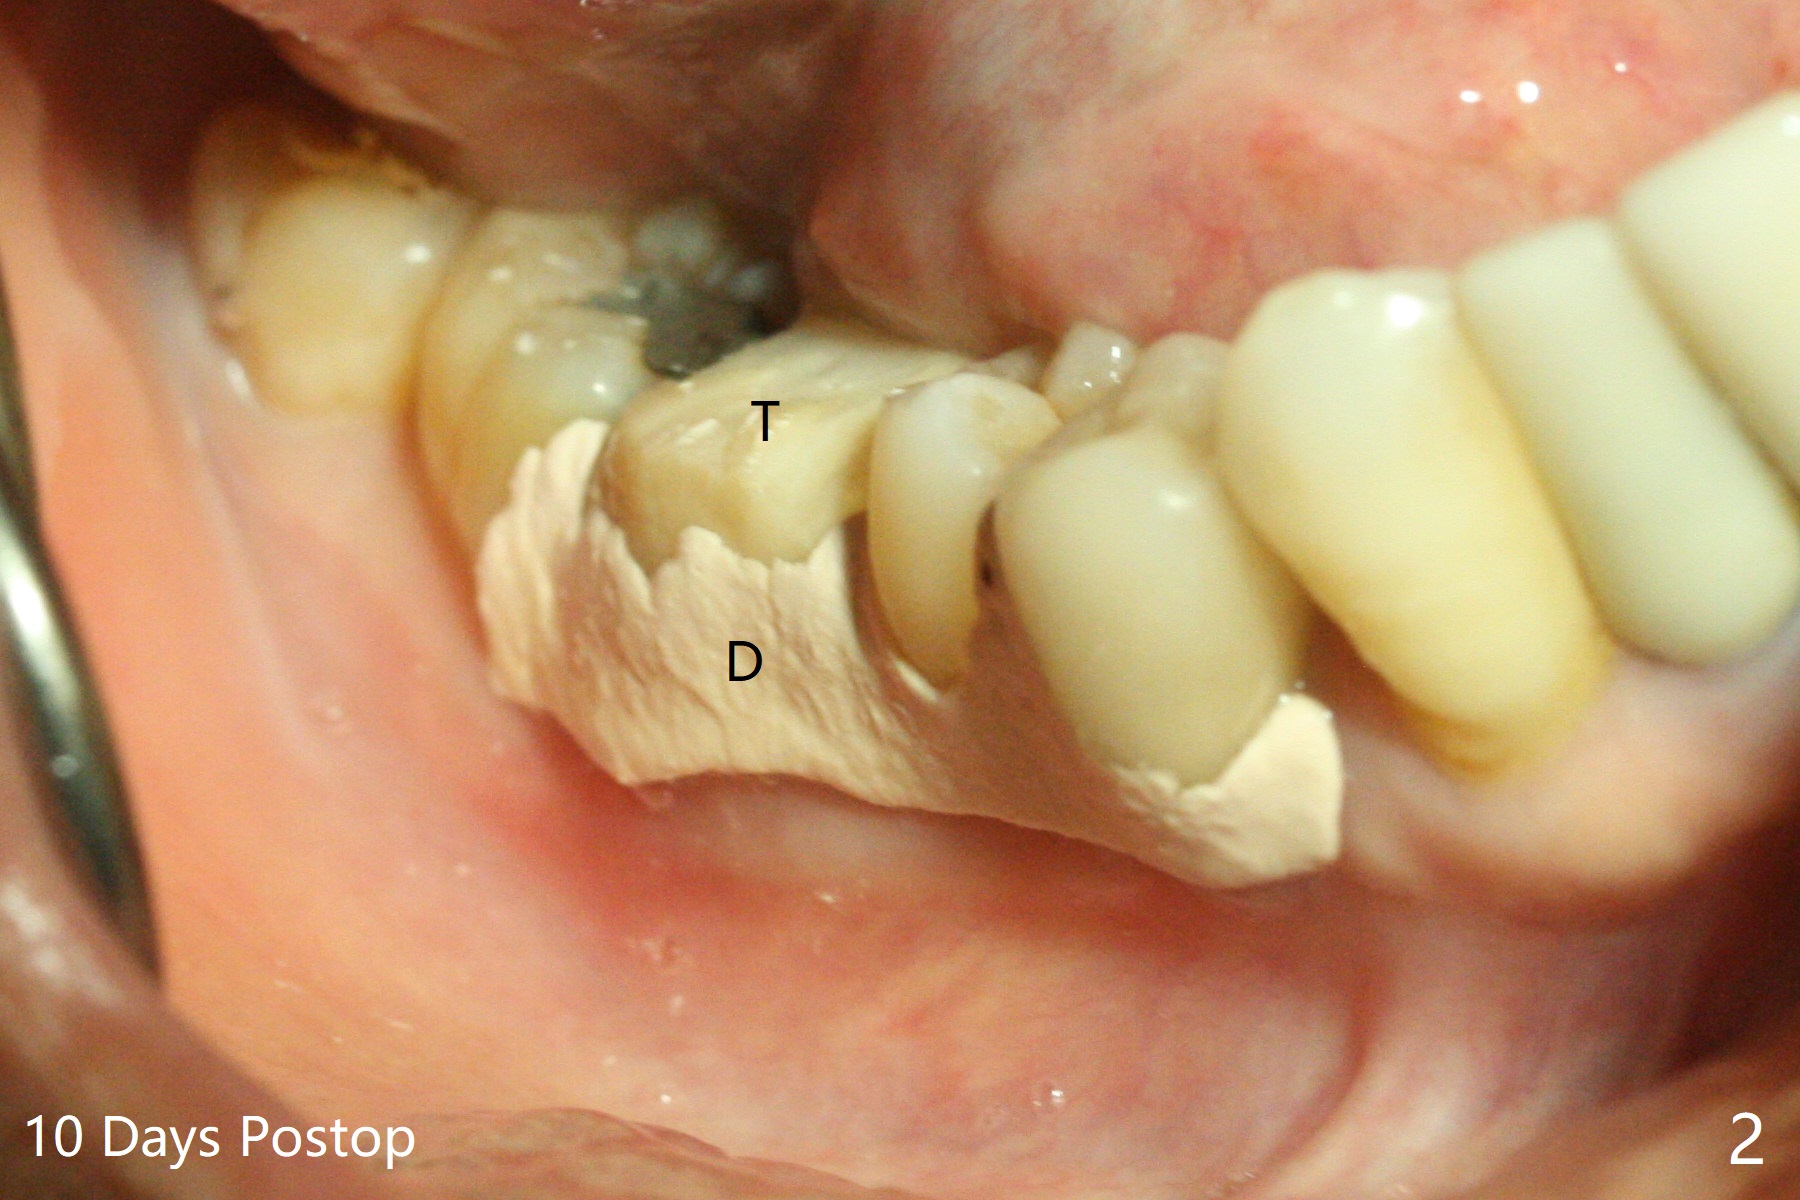

In spite of severe bone loss and 1.86 mm remaining bone after extraction of the tooth #30, a 5x7.3 mm implant achieves insertion torque of 35 Ncm with an immediate provisional (Fig.1). Periodontal dressing is applied for additional fixation of the bone graft (*) and Osteogen plug (P). Although the implant is placed in the mesial socket, the coronal end of the abutment is in the middle of the edentulous area. The patient is extremely pleased with no pain surgery. There is no postop paresthesia. The periodontal dressing (Fig.2 D) remains in place and buccal to the temporary crown (T) 10 days postop. When the former is removed, there is a gap between the margin of the provisional and that of the gingiva (Fig.3 between arrow and arrowhead), suggesting that the latter has shrunk postop. If there were no periodontal dressing, some of bone graft may have been lost. The distal socket heals when the immediate provisional is removed for revision 5 weeks postop (Fig.4). With gingival retraction cords, the abutment margin is prepared 2 months postop, particularly distal, to reduce food impaction in the future. If there is no abutment screw loosening with final restoration, it suggests that computer designed trajectory is acceptable. The implant plateau seems to be covered by the bone 4.5 months postop (Fig.5). In fact the mesiobuccal margin of the abutment is close to the corresponding crestal bone. The gingiva looks healthy 5 months postop (immediately before cementation, Fig.6), although MO amalgam of the tooth #31 is breaking down (*). Return to Lower Molar Immediate Implant, Prevent Molar Periimplantitis (Protocols, Table), Trajectory Xin Wei, DDS, PhD, MS 1st edition 04/17/2019, last revision 09/14/2019